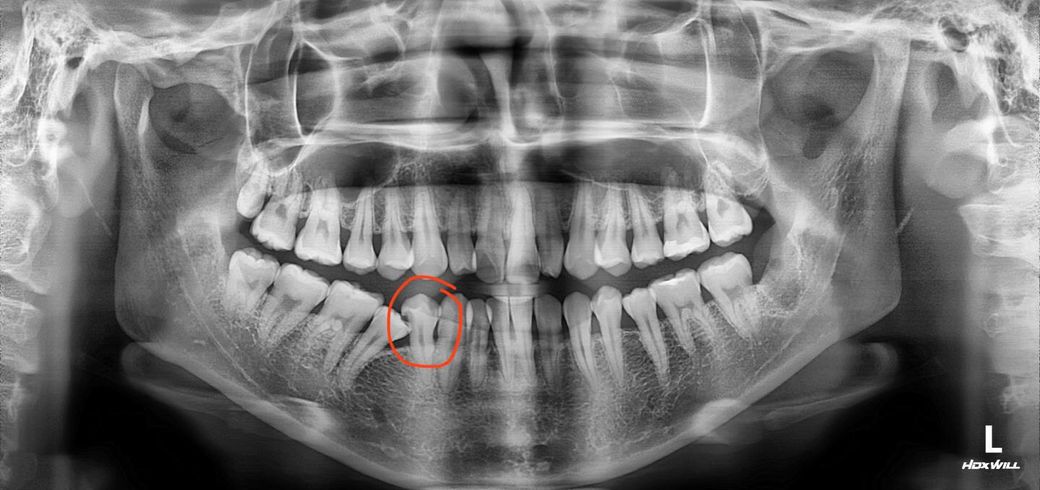

제가 치과 진료를 받는데 동그라미 쳐진 이빨의 신경과 충치가 가까워서 신경치료를 해야 한다고 하더라구요. 밑에 첨부사진은 그 치과에서 받아온 엑스레이 사진입니다.

사진상으로 보면 괴장이 안좋은 부위가 썩어 있으신거 같습니다. 제 생각에도 신경치료를 하셔야될것같습니다.

신경치료를 해야할 수도 있고 아닐수도 있는 중간 단계로 보여집니다. x-ray 상으로는 신경과 근접하지 않아 보이긴 하나 이는 충치 부위를 제거하다 보면 신경과 상당히 근접할 가능성도 높습니다. 신경과 근접하다보면 신경치료의 가능성을 열어두고 치료를 하셔야 합니다. 즉 모조건 신경치료를 하는 것은 아니나 아마 앞서 방문하신 치과에서는 예방적으로 말씀하신 것으로 보입니다.

엑스레이 사진으로볼때, 해당치아에 충치가 깊어서, 치료하려면 신경치료를 해야할 가능성이 매우 높은것으로 보입니다.

하지만 만약 방사선사진을 찍어보지 않고 눈으로만 검사를 했다면 충치를 발견하지 못했을 수 도 있습니다.